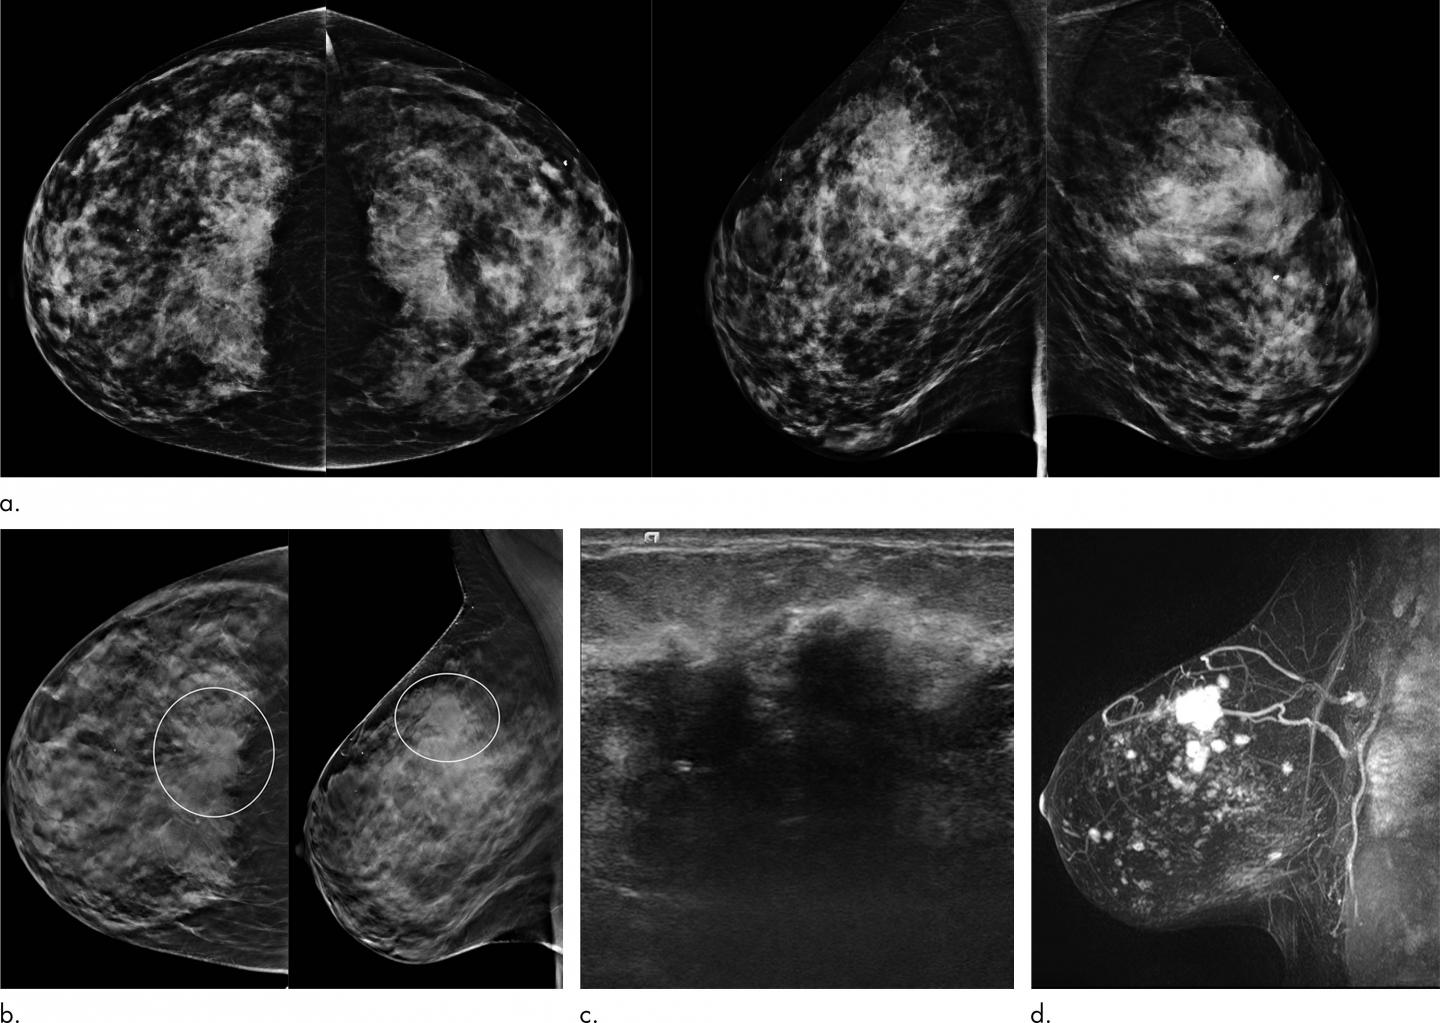

OAK BROOK, Ill. - A new study published in the journal Radiology has found that the advantages of digital breast tomosynthesis (DBT) over digital mammography (DM), including increased cancer detection and fewer false positive findings, are maintained over multiple years and rounds of screening. In addition, research showed that DBT screening helped detect a higher proportion of poor prognosis cancers than DM.

DBT, sometimes called 3D mammography, emerged in the last decade as a powerful tool for breast cancer screening. The procedure uses an X-ray tube that moves in an arc and takes low radiation-dose projections of the breast from different angles. Varying the angle allows for multiple data points that can be reconstructed in different ways.

"As a radiologist, tomosynthesis allows viewing of the breast in multiple layers or slices," said study lead author Emily F. Conant, M.D., professor and chief of breast imaging in the Department of Radiology, Perelman School of Medicine at the University of Pennsylvania in Philadelphia. "This ability to scroll through slices of otherwise overlapping breast tissue helps us not only detect more cancers but also better characterize benign or normal areas of the breast."

Dr. Conant attributed the improved outcomes achieved with tomosynthesis to better visualization of both benign and malignant lesions and a reduction in tissue superimposition.

"With tomosynthesis you can remove some of the overlapping or obscuring breast tissue so that both normal and abnormal findings are better seen," she said. "That provides both improved cancer detection and decreased false positives."